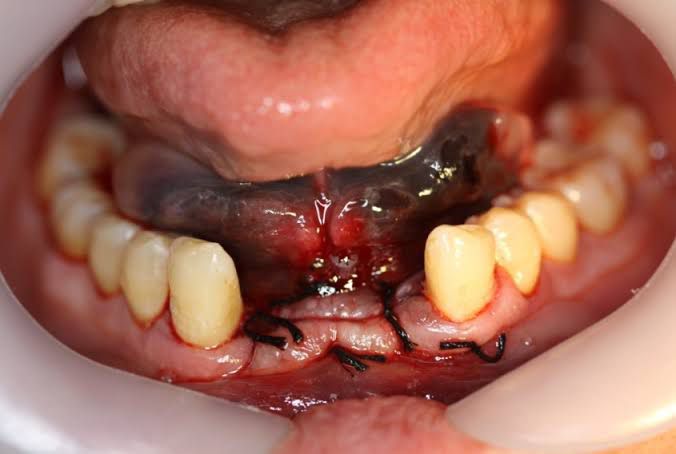

Like any surgery, dental implant surgery poses some health risks. Problems are rare, though, and when they do occur they're usually minor and easily treated. Risks include: Infection at the implant site Injury or damage to surrounding structures, such as other teeth or blood vessels Nerve damage, which can cause pain, numbness or tingling in your natural teeth, gums, lips or chin Sinus problems, when dental implants placed in the upper jaw protrude into one of your sinus cavities